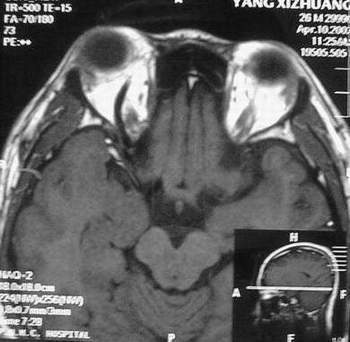

MRI及增强结果如下:

患者压颈及其它Valsava试验结果阴性。从MRI分析,在T1、T2、T+C检查该支血管均为明显流空现象,说明该血管血流速度很快,而从走行和分布看,眼上静脉可能性很大。也许也不能除外异常的眼动脉或异常血管。眶内主要可能的血管病变包括颈内动脉海绵窦瘘(高流窦)、AVM、眼眶静脉曲张、海绵状血管瘤、静脉性血管瘤、毛细血管瘤和眶内动脉瘤。。 1、颈内动脉海绵窦瘘:该患者临床有一部分支持该诊断。但从影像分析,海绵窦未见明显扩张;眼外肌未见明显充血扩张的长T1、长T2信号;颈内动脉海绵窦瘘常可见继发到血栓,可见到短T1、长T2的血栓信号。 2、眼眶静脉曲张:该疾患一般常见于小儿。该患大多数会出现Valsava试验阳性,间歇性突眼。不符合该患。影像学检查,于曲张静脉内常可见血栓和静脉石。所以不符合该患。 3、AVM:患者目前的影像学资料尚不全面,但可符合该诊断。临床上改病常见于30岁左右年轻人,单侧发病,于本患较符合。问题在于临床没有明确的血管杂音,似乎难以解释。 4、该患影像学与海绵状血管瘤差别很大,所以可基本排除此诊断。 5、静脉性血管瘤和毛细血管瘤:MRI中等T1、长T2信号,较易与本病鉴别。 6、眶内动脉瘤:我觉得患者并不能排除本病,但同样,由于波动性阴性,似乎也难以解释。 纵上所述:本人觉得,患者AVM可能性较大,同时不能除外眶内动脉瘤。 关于进一步检查,我觉得DSA价格过于昂贵。是否可先进行彩色多普勒检查,首先可以明确是静脉系统还是动静脉瘘抑或是动脉瘤。第二步,可进行MRA检查,可以清楚地显示海绵窦地相关关系,并可借此诊断或排除颈内动脉海绵窦瘘。如还需第三部检查,可进行MRV检查,对静脉系统进一步评价。三种检查总共的费用2000多圆,但给予我们的信息量已经很丰富了。 敬请各位医师提出自己的见解。 谢谢!